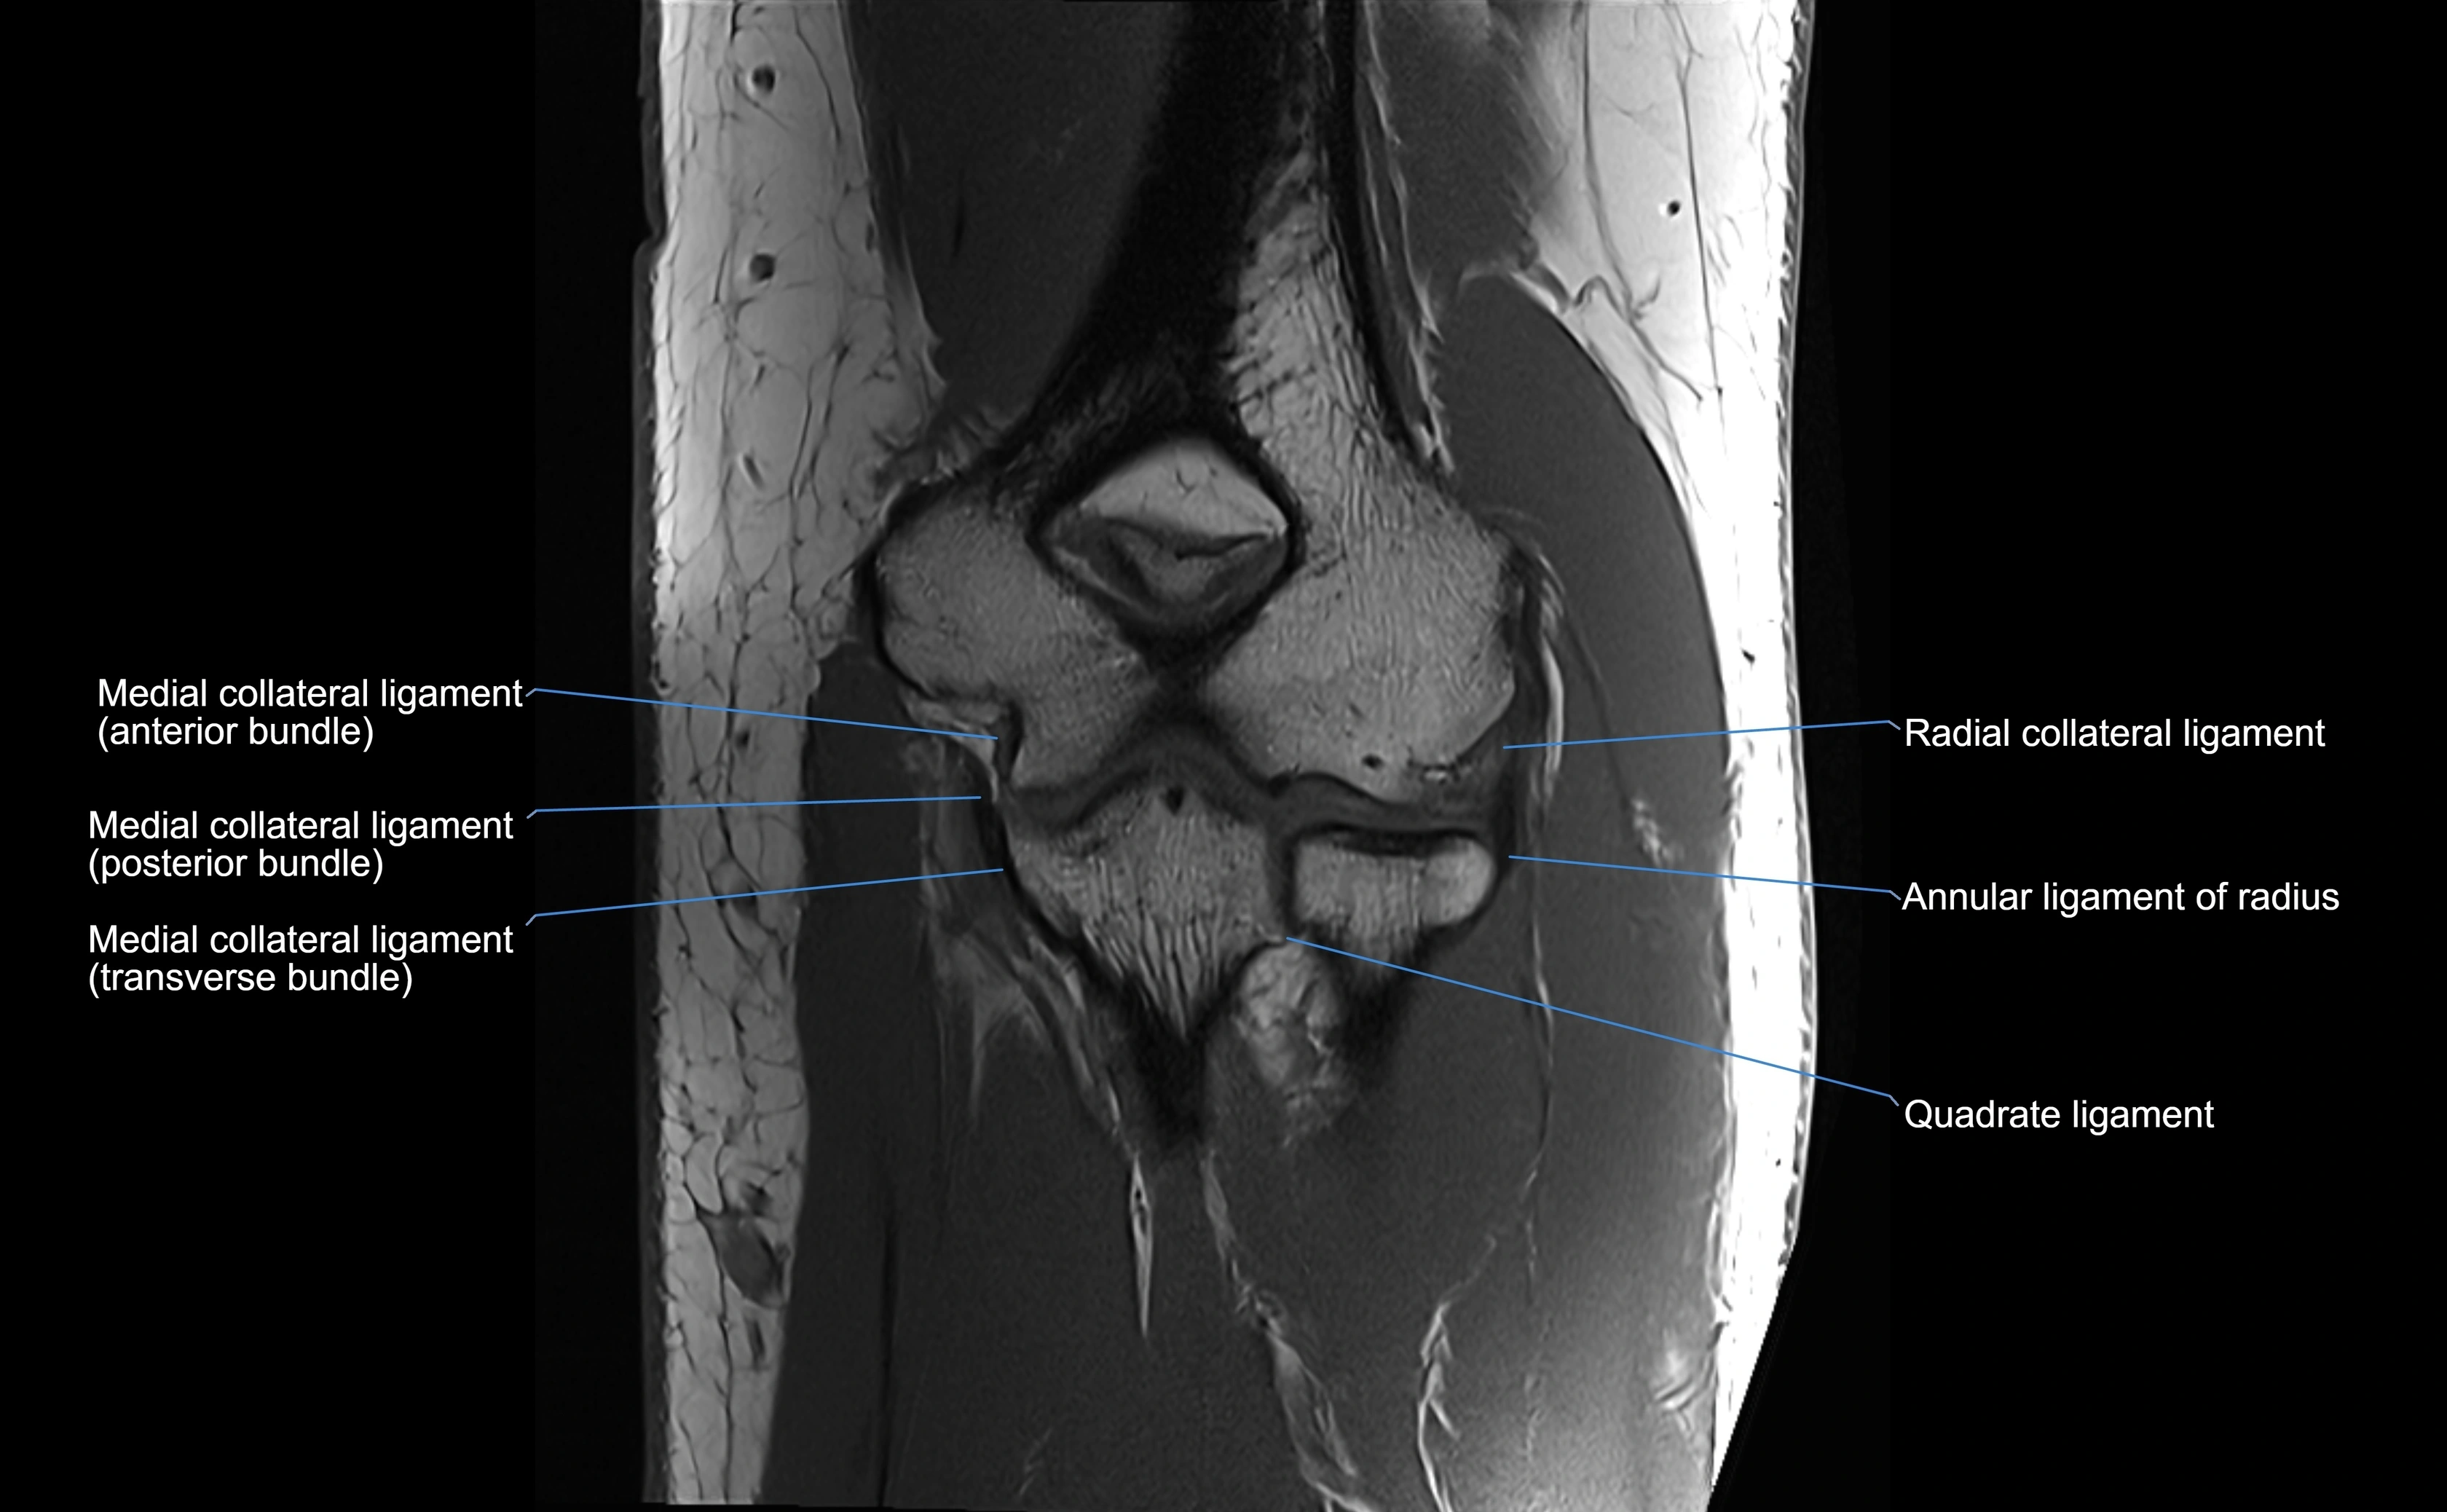

T1 Fat-Sat Post-Contrast:

• Normal: minimal enhancement.

• Inflamed or injured ligament: focal or diffuse enhancement.

• Synovial enhancement in chronic instability or post-surgical changes.

MRI Arthrogram Appearance

• Contrast outlines the proximal radioulnar joint and radial head recess.

• Normal ligament appears as a dark ring surrounding the radial head, containing the injected contrast within the joint cavity.

• Partial tear: contrast extends along the ligament or beneath its fibers.

• Complete tear or subluxation: contrast extravasates around the radial head or ulna, indicating discontinuity.

• Detects capsular defects, instability, or synovial invagination with high sensitivity.

MRI images

image